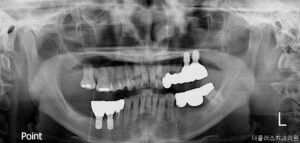

전체적인 검진 결과,

전반적인 치주 상태가 좋지 않았으며,

가장 시급한 부분은

치아가 빠진 이후 방치한 시간이

길어지다 보니 오른쪽과 왼쪽 아래 어금니들은

모두 쓰러지며 누워있는

형태를 띠었고 머리 부분이

완전히 파절된 부분도 눈에 띄었습니다.

또한 오른쪽 위 큰 어금니의 경우

아래의 대합치가 없어

정출된 상태였습니다.